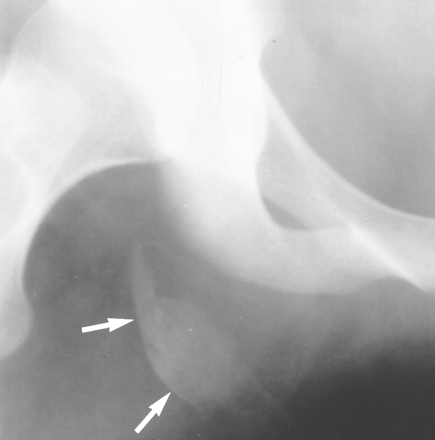

Ischial Avulsion

This can mimic a simple hamstring strain, although there is usually more bruising. Most patients are treated conservatively. If the displacement is more than 2 cm then internal fixation is indicated.